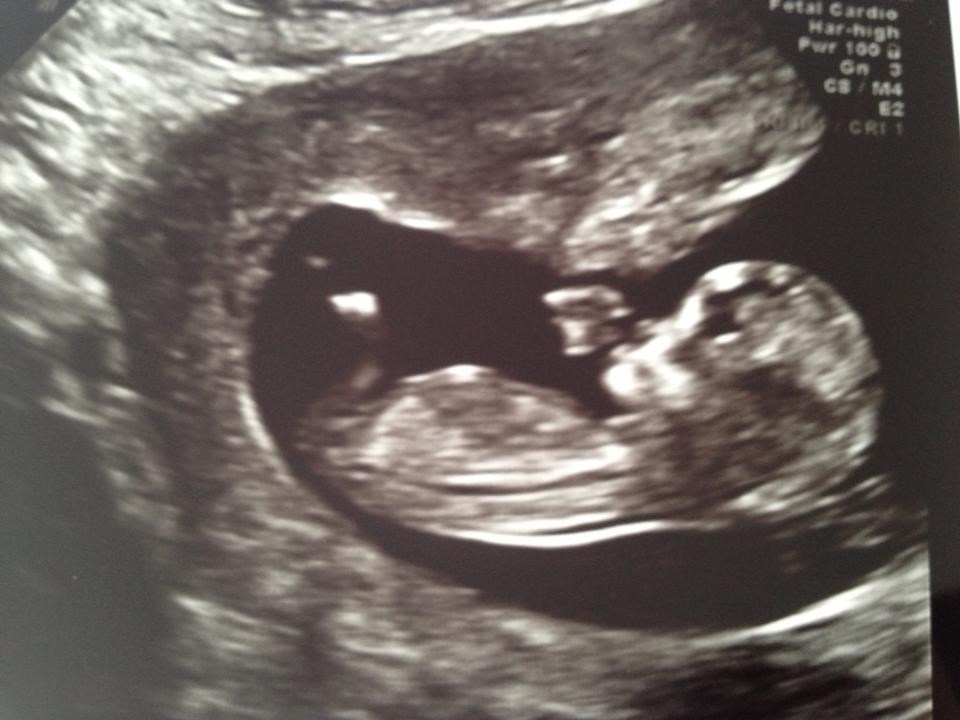

Vi skal til kønsscanning d. 28

Tror det er endnu en dreng vi venter. Synes jeg så en lille tap der vente nedad

Mavefornemmelsen siger dog pige, meeeeen det gjorde den ogsp ved Lukas

Uuh hvor spændende! Spændende at se om du faktisk så en lille tap, eller om I måske også skal have en lillesøster..

Hehe, ja den mavefornemmelse holder alligevel ikke altid stik.. Jeg drømte jo jeg fik en dreng, da jeg var gravid med Frej, så det passede jo fint.. Men jeg drømte også jeg fik en dreng i denne graviditet og det holdt jo så altså ikke rigtig stik..